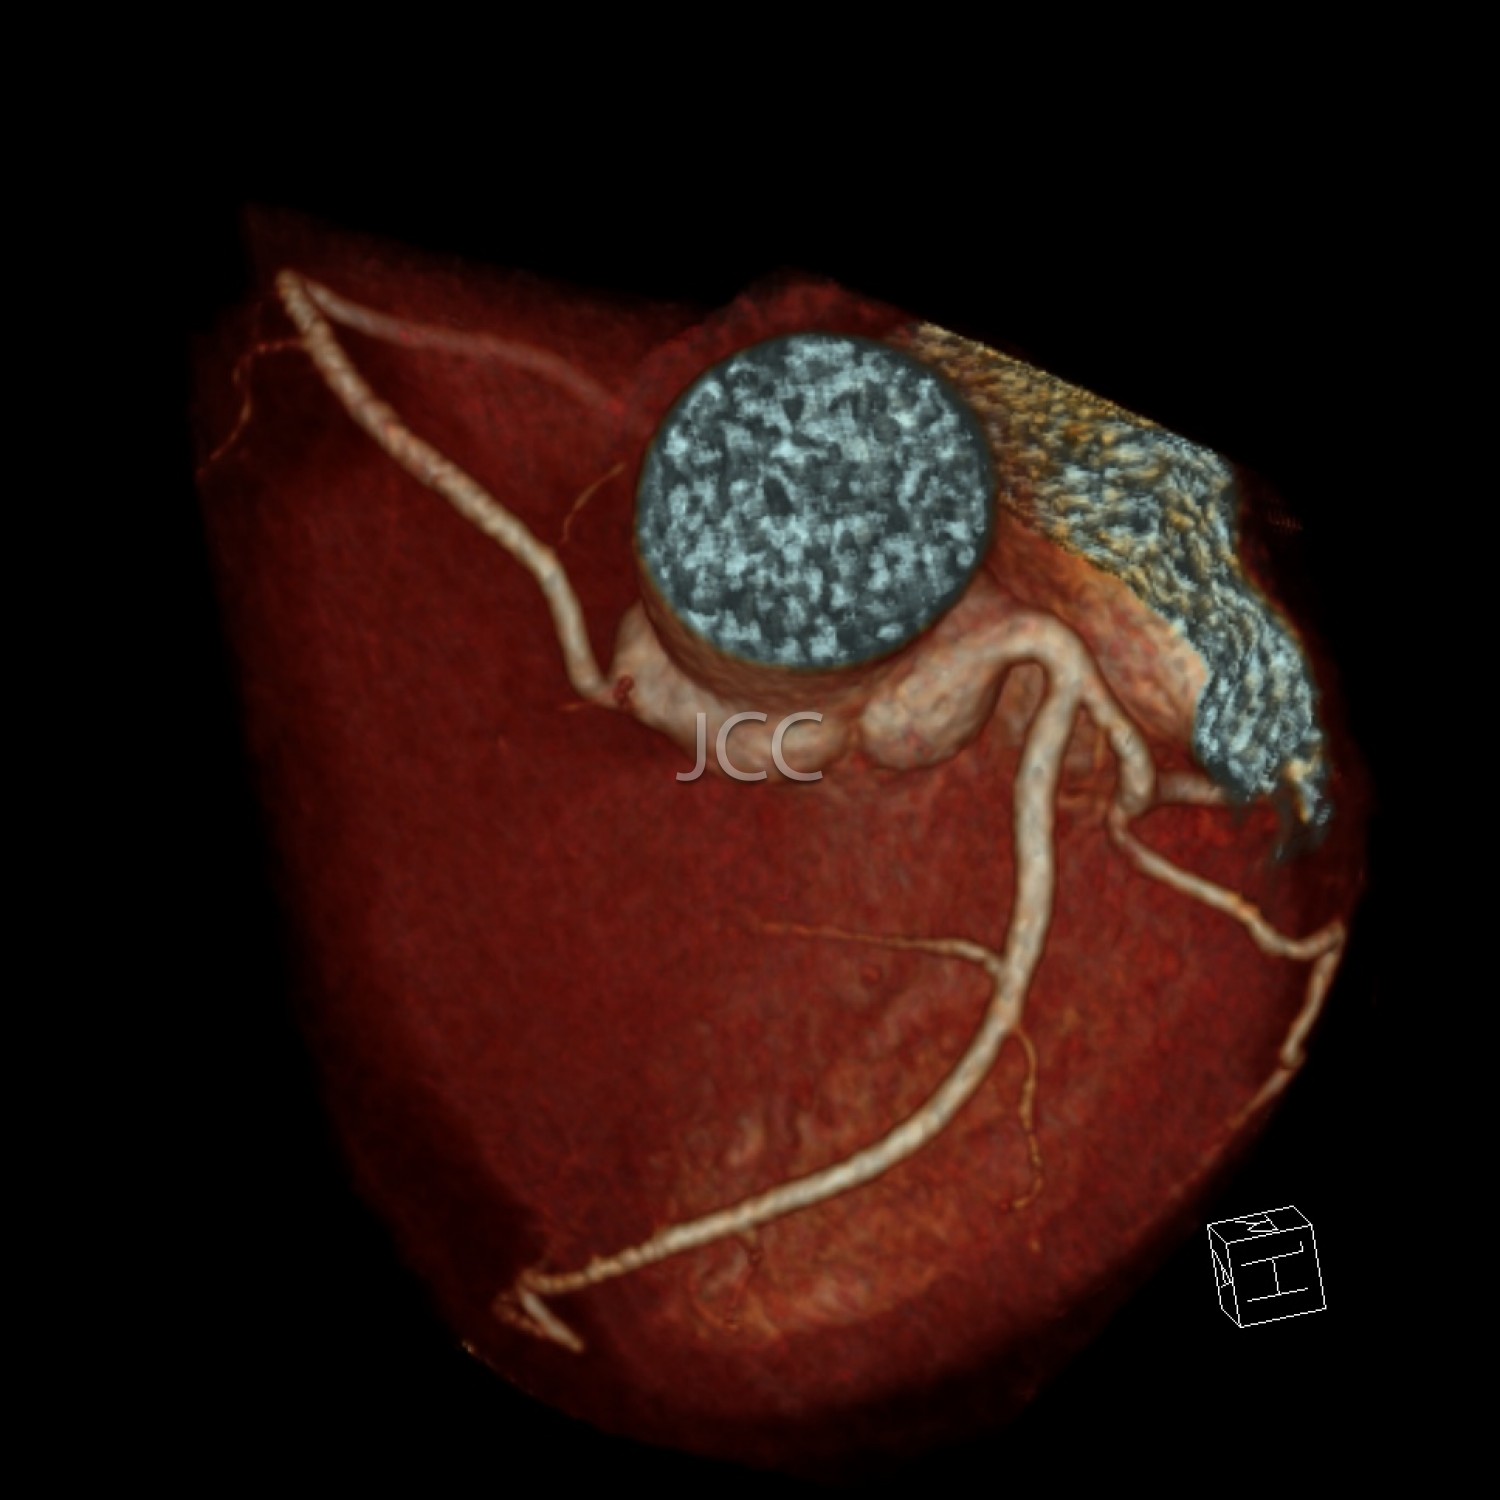

Tomografia Axial Computorizada - ANGIO TAC CORONÁRIAS

A Tomografia Axial Computorizada (TAC) - Dupla Energia - 256 cortes é uma técnica de diagnóstico que permite a avaliação de várias partes do corpo humano, incluindo pulmões, fígado, pâncreas, rins, coração, estruturas vasculares e estruturas ósseas.

Os nossos equipamentos são todos de multicorte permitindo avaliação em alta definição e baixa dose de radiação incluindo o estudo das coronárias.